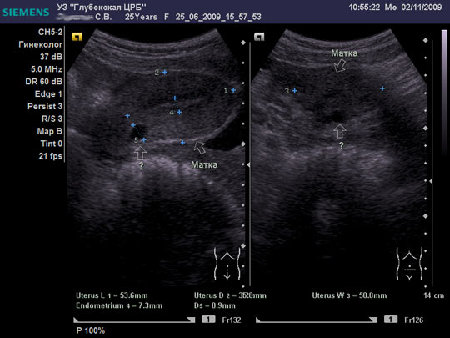

Женщина 25 лет предъявляет жалобы на периодически возникающую болезненность в нижних отделах живота, боли появились около 6-8 мес. Менструальная функция не нарушена. В анамнезе кесарево сечение, ребёнку 2,5 года.

- Сонограмма после курса противовоспалительной терапии

Doc, на взгляд неспециалиста в гинекологическом УЗИ -

Nabothian cyst

Я тоже думал про наботовы желёзки, но меня смутил тот момент, что не явилось ли это образование следствием оперированной матки, лигатуры... ну чего-то там с ними... или что-то в этом духе????

Согласен, Наботова или эндо-цервикальная киста шейки. Ничего специфического.

Naboti пишем, эндометриоз в уме